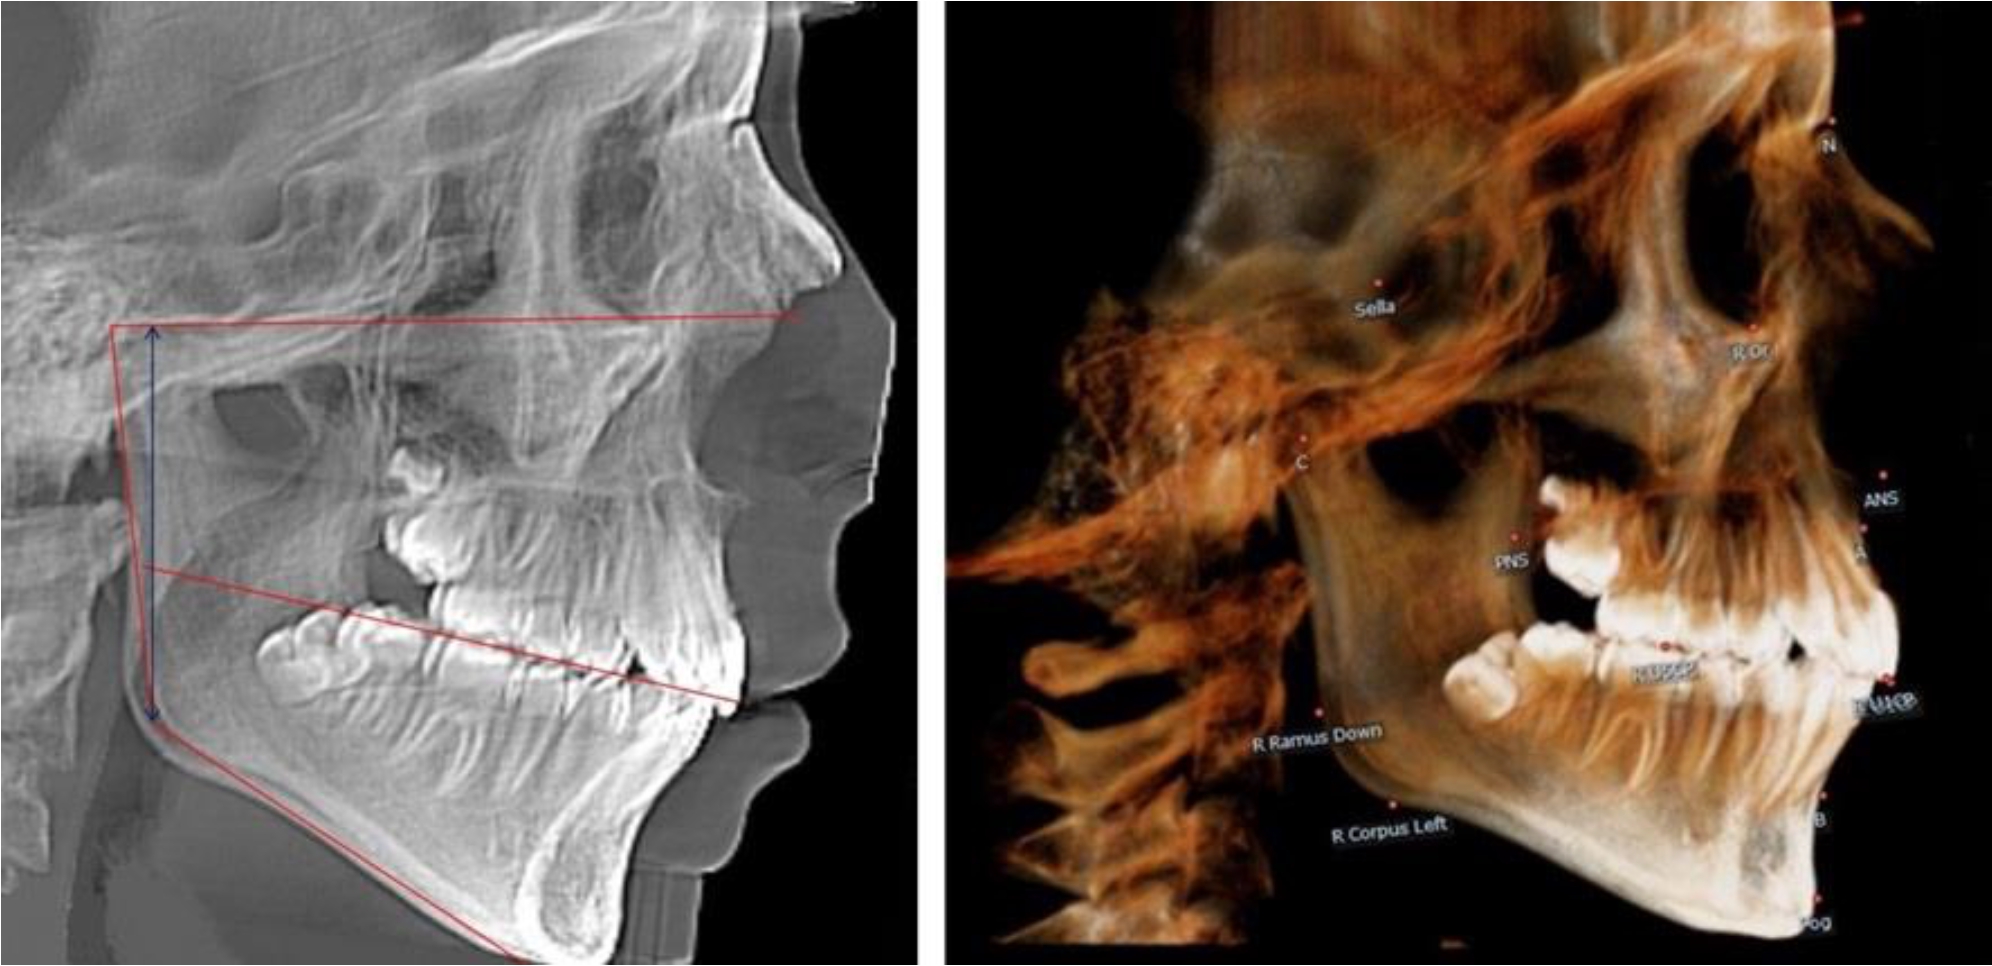

В 4-й группе были проанализированы 12 комплектов рентгенограмм, что составило (11,32 ± 3,08) % от общего числа. На всех рентгенограммах произошла полная смена всех молочных зубов постоянными. Окклюзионная линия делила ветвь на два отдела (рис. 4).

Рис. 4. ТРГ пациента после смены всех молочных резцов

Высота ветви у детей 4-й группы составляла (54,27 ± 2,59) мм, что было достоверно больше, чем у детей 1-й группы (р ˂ 0,05). При этом высота верхней окклюзионно-суставной части была (32,51 ± 1,72) мм, а нижней – (21,76 ± 1,42) мм. Высота верхней части была больше нижней, что и определяло особенности соразмерности частей ветви нижней челюсти в анализируемый возрастной период.

Относительные показатели соразмерности частей ветви нижней челюсти показали, что отношение высоты верхней части ветви к нижней в среднем составляло 1,49 ± 0,12. Отношение общей высоты ветви к верхней ее части составляло 1,67 ± 0,14, а отношение общей высоты ветви к нижней ее части было 2,49 ± 0,15, что и определяло особенности соразмерности частей ветви нижней челюсти в анализируемый возрастной период.

В 5-й группе были проанализированы 14 комплектов рентгенограмм, что составило (13,21 ± 3,29) % от общего числа. На всех рентгенограммах отмечен очередной этап подъема высоты прикуса, обусловленный прорезыванием вторых постоянных моляров. Окклюзионная линия делила ветвь на два отдела (рис. 5).

Рис. 5. ТРГ и ОПТГ пациента после смены молочных зубов и прорезывания вторых постоянных моляров

Высота ветви у детей 5-й группы составляла (62,87 ± 3,62) мм, что было достоверно больше, чем у детей других групп (р ˂ 0,05). При этом высота верхней окклюзионно-суставной части была (40,23 ± 2,01) мм, а нижней – (22,64 ± 1,78) мм. Высота верхней части была вдвое больше нижней, что и определяло особенности соразмерности частей ветви нижней челюсти в анализируемый возрастной период.

Относительные показатели соразмерности частей ветви нижней челюсти показали, что отношение высоты верхней части ветви к нижней в среднем составляло 1,78 ± 0,18. Отношение общей высоты ветви к верхней ее части составляло 1,56 ± 0,12, а отношение общей высоты ветви к нижней ее части было 2,78 ± 0,14, что и определяло особенности соразмерности частей ветви нижней челюсти в анализируемый возрастной период.